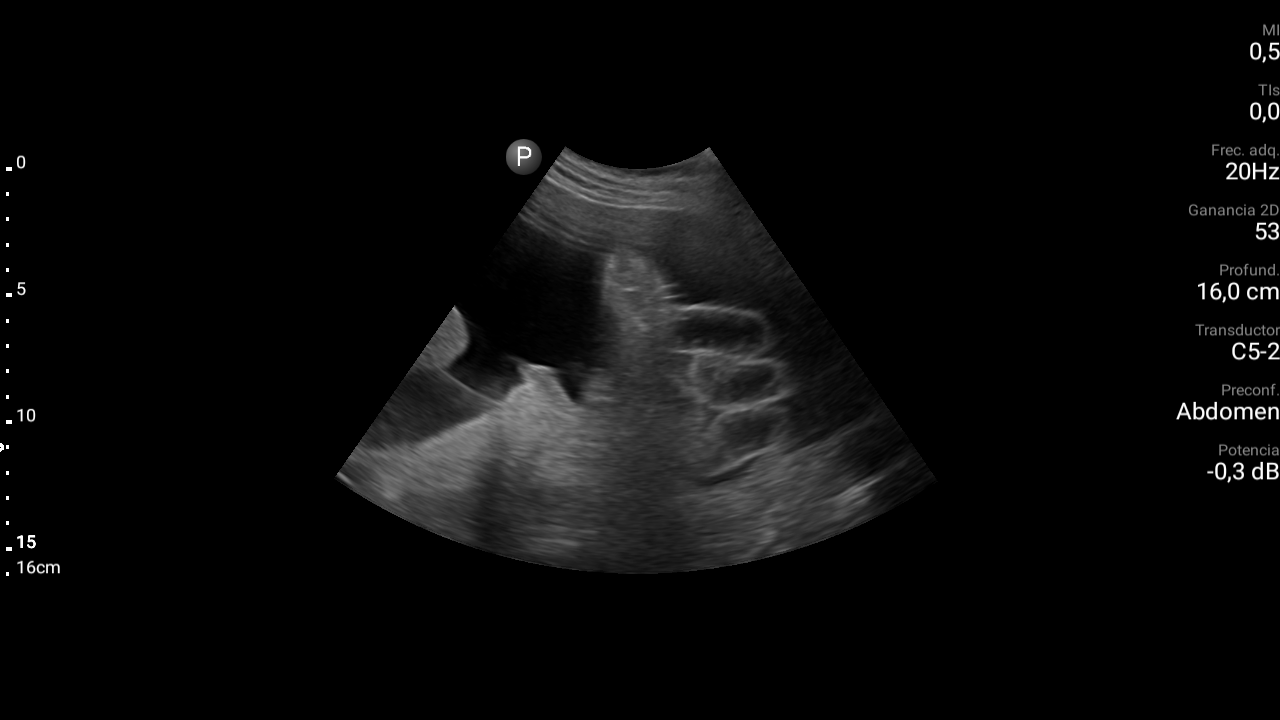

Presencia de ascitis perihepática, periesplénica. En la pelvis se visualizan asas intestinales con aspecto congestivo.

Hígado parcialmente visualizado esteatósico sin lesiones focales.

Derrame pleural bilateral moderado.

TC abdominal: Estigmas de hepatopatía severa (hígado de bordes nodulares e hipertrofia del lóbulo caudado) Ascitis peritoneal. Aspecto congestivo asas de delgado. Estigmas de hipertensión portal con circulación colateral destacando presencia de varices rectales. Derrame pleural bilateral